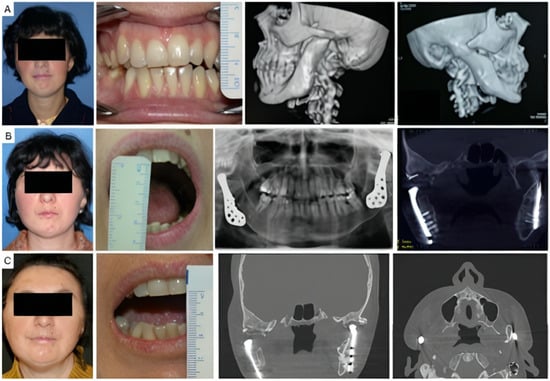

Four patients had not undergone previous surgical treatments, while 21 had undergone one to three prior surgeries. Three patients had more than three interventions. Of these, 13 underwent coronoidectomy, 10 underwent arthroplasty without material interposition, 7 experienced maxillo-facial fractures osteosynthesis, 2 had condylectomies, 2 mandibular distraction, 4 costochondral grafts, 1 an iliac crest graft, 2 arthroplasty with silastic interposition, 1 dermal fat interposition, and 2 had previous total joint replacements with stock prostheses. Three patients’ cases are illustrated in Figure 2, Figure 3 and Figure 4.

Figure 4. Clinical case of TMJ ankylosis caused by perinatal infection, treated by stock TMJ prostheses. (A) Clinical frontal preoperative view, preoperative maximum interincisal opening of patient (less than 1 cm) and preoperative 3D TC scan, that shows bilateral ankylosis. (B) Postoperative clinical view, maximum interincisal opening (3 cm) and postoperative radiographs of the patient at 2 years follow up. (C) Postoperative clinical view, maximum interincisal opening of patient (1.5 cm) and postoperative radiographs at 17 years follow up.